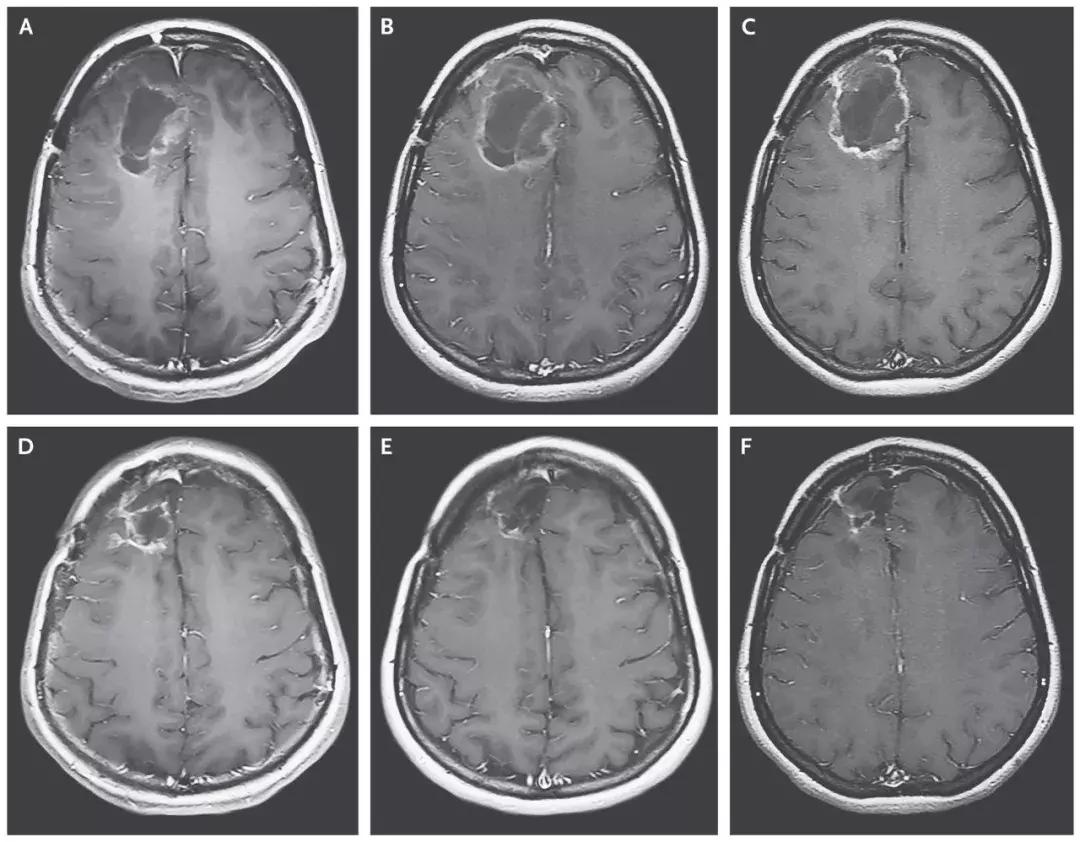

研究人员在一项1期临床试验中,总共招募了61名患者,并在他们的头骨上设置了导管,让病毒得以直接进入大脑,攻击肿瘤。CD155在胶质母细胞瘤中有高度表达,而这种经过处理的病毒能针对表达CD155的肿瘤细胞,选择性地入侵并进行复制,最终导致肿瘤细胞的裂解。

截止2018年3月20日,8名患者对治疗产生治疗应答,2名患者的脑胶质瘤病灶完全消失,达到了完全缓解!

▲患者脑部肿瘤的缩小清晰可见(图片来源:《NEJM》)

这位患者,经过PVSRIPO溶瘤病毒治疗7个月后,病情复发后使用洛莫司汀治疗,经过12个月的洛莫司汀治疗后,病人的病灶完全消失并保持了20个月的无病状态,并且在PVSRIPO溶瘤病毒治疗发生出血后57.5个月仍然存活。